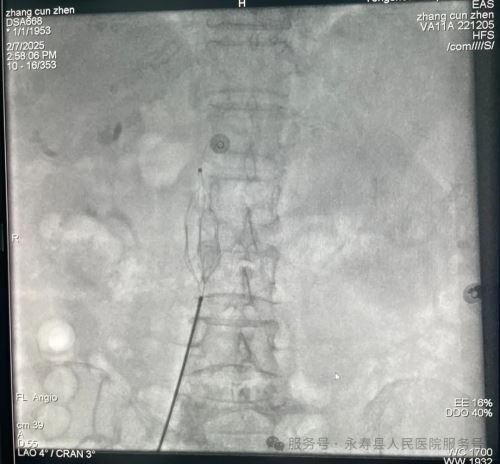

手术在上级医院专家的协助及介入科团队辅助下进行,为患者行下腔静脉滤器植入术,经股静脉植入鞘管。造影下腔静脉无血栓形成,肺动脉造影显示右上肺动脉(小动脉)中远段肺栓塞形成,肺栓塞诊断明确,是下腔静脉滤器植入绝对适应症,确定滤器的适宜型号和释放系统后,在肾静脉下端置入下腔静脉滤器,并确认其位置完好。整个手术过程历时仅30分钟,患者无不适反应,经后续治疗效果良好。

下腔静脉滤器置入